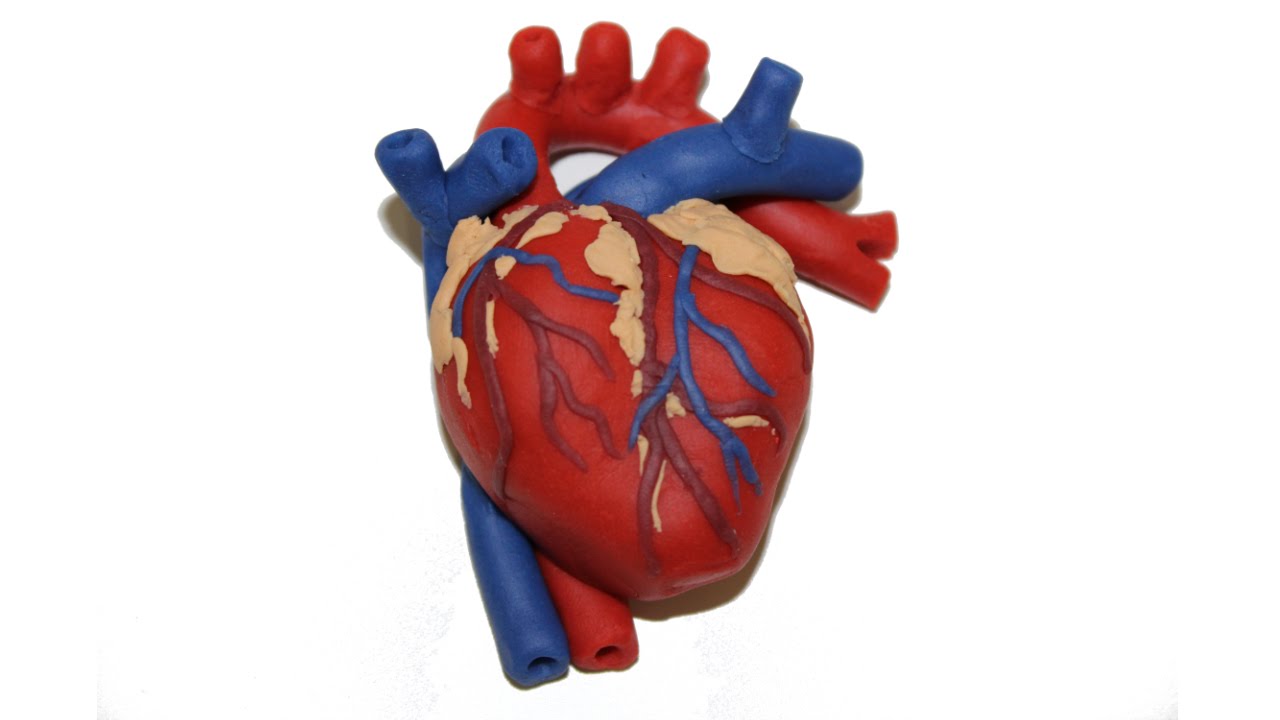

Фотографии и 3D-модели анатомии сердца человека